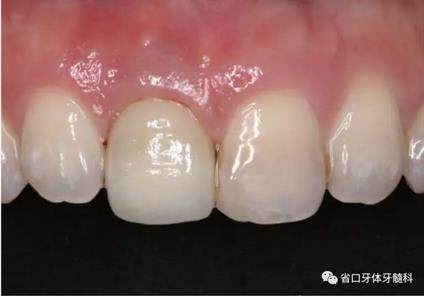

(4)最終修復(fù)與隨訪:經(jīng)過3個(gè)月左右的塑形,上頜右側(cè)中切牙臨時(shí)修復(fù)固位良好,菌斑控制良好,近遠(yuǎn)中齦乳頭充盈良好,齦緣水平及形態(tài)與 鄰牙相對稱。牙齦塑形穩(wěn)定后,以臨時(shí)修復(fù)體制作個(gè)性化轉(zhuǎn)移桿并取模轉(zhuǎn)移,并以原廠氧化鋯基臺(tái)制備個(gè)性化基臺(tái)及全瓷冠。正確就位最終基臺(tái),加 力30N·cm。制備粘接代型,去除多余粘接劑,以Unicem粘接固位上頜右側(cè)中切牙全瓷修復(fù)體。固化穩(wěn)定后,再次確定咬合無干擾。最終修復(fù)完成后 隨訪3個(gè)月及6個(gè)月,上頜右側(cè)中切牙種植修復(fù)固位穩(wěn)定,近遠(yuǎn)中齦乳頭充 盈良好,唇側(cè)齦緣水平穩(wěn)定。

圖30 塑形完成

圖33 就位全瓷冠

圖34 負(fù)重3個(gè)月后